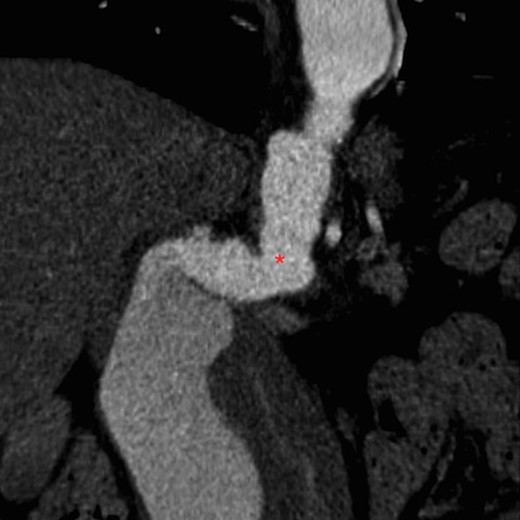

On arrival at our hospital, she was hemodynamically stable, with all vital signs within the normal range. Abdominal examination revealed a pulsating mass in the center of the abdomen. A computed tomography (CT) angiogram of aorta was performed for further evaluation that showed ectatic aorta from arch to the diaphragm. There was an 8.7-cm infra-abdominal AAA with extension into both common iliac arteries. The aneurysm neck was tortuous with an acute angle making endovascular repair challenging (Figs 1–4).

Coronal view of CT aortogram showing compression of IVC (asterisk).